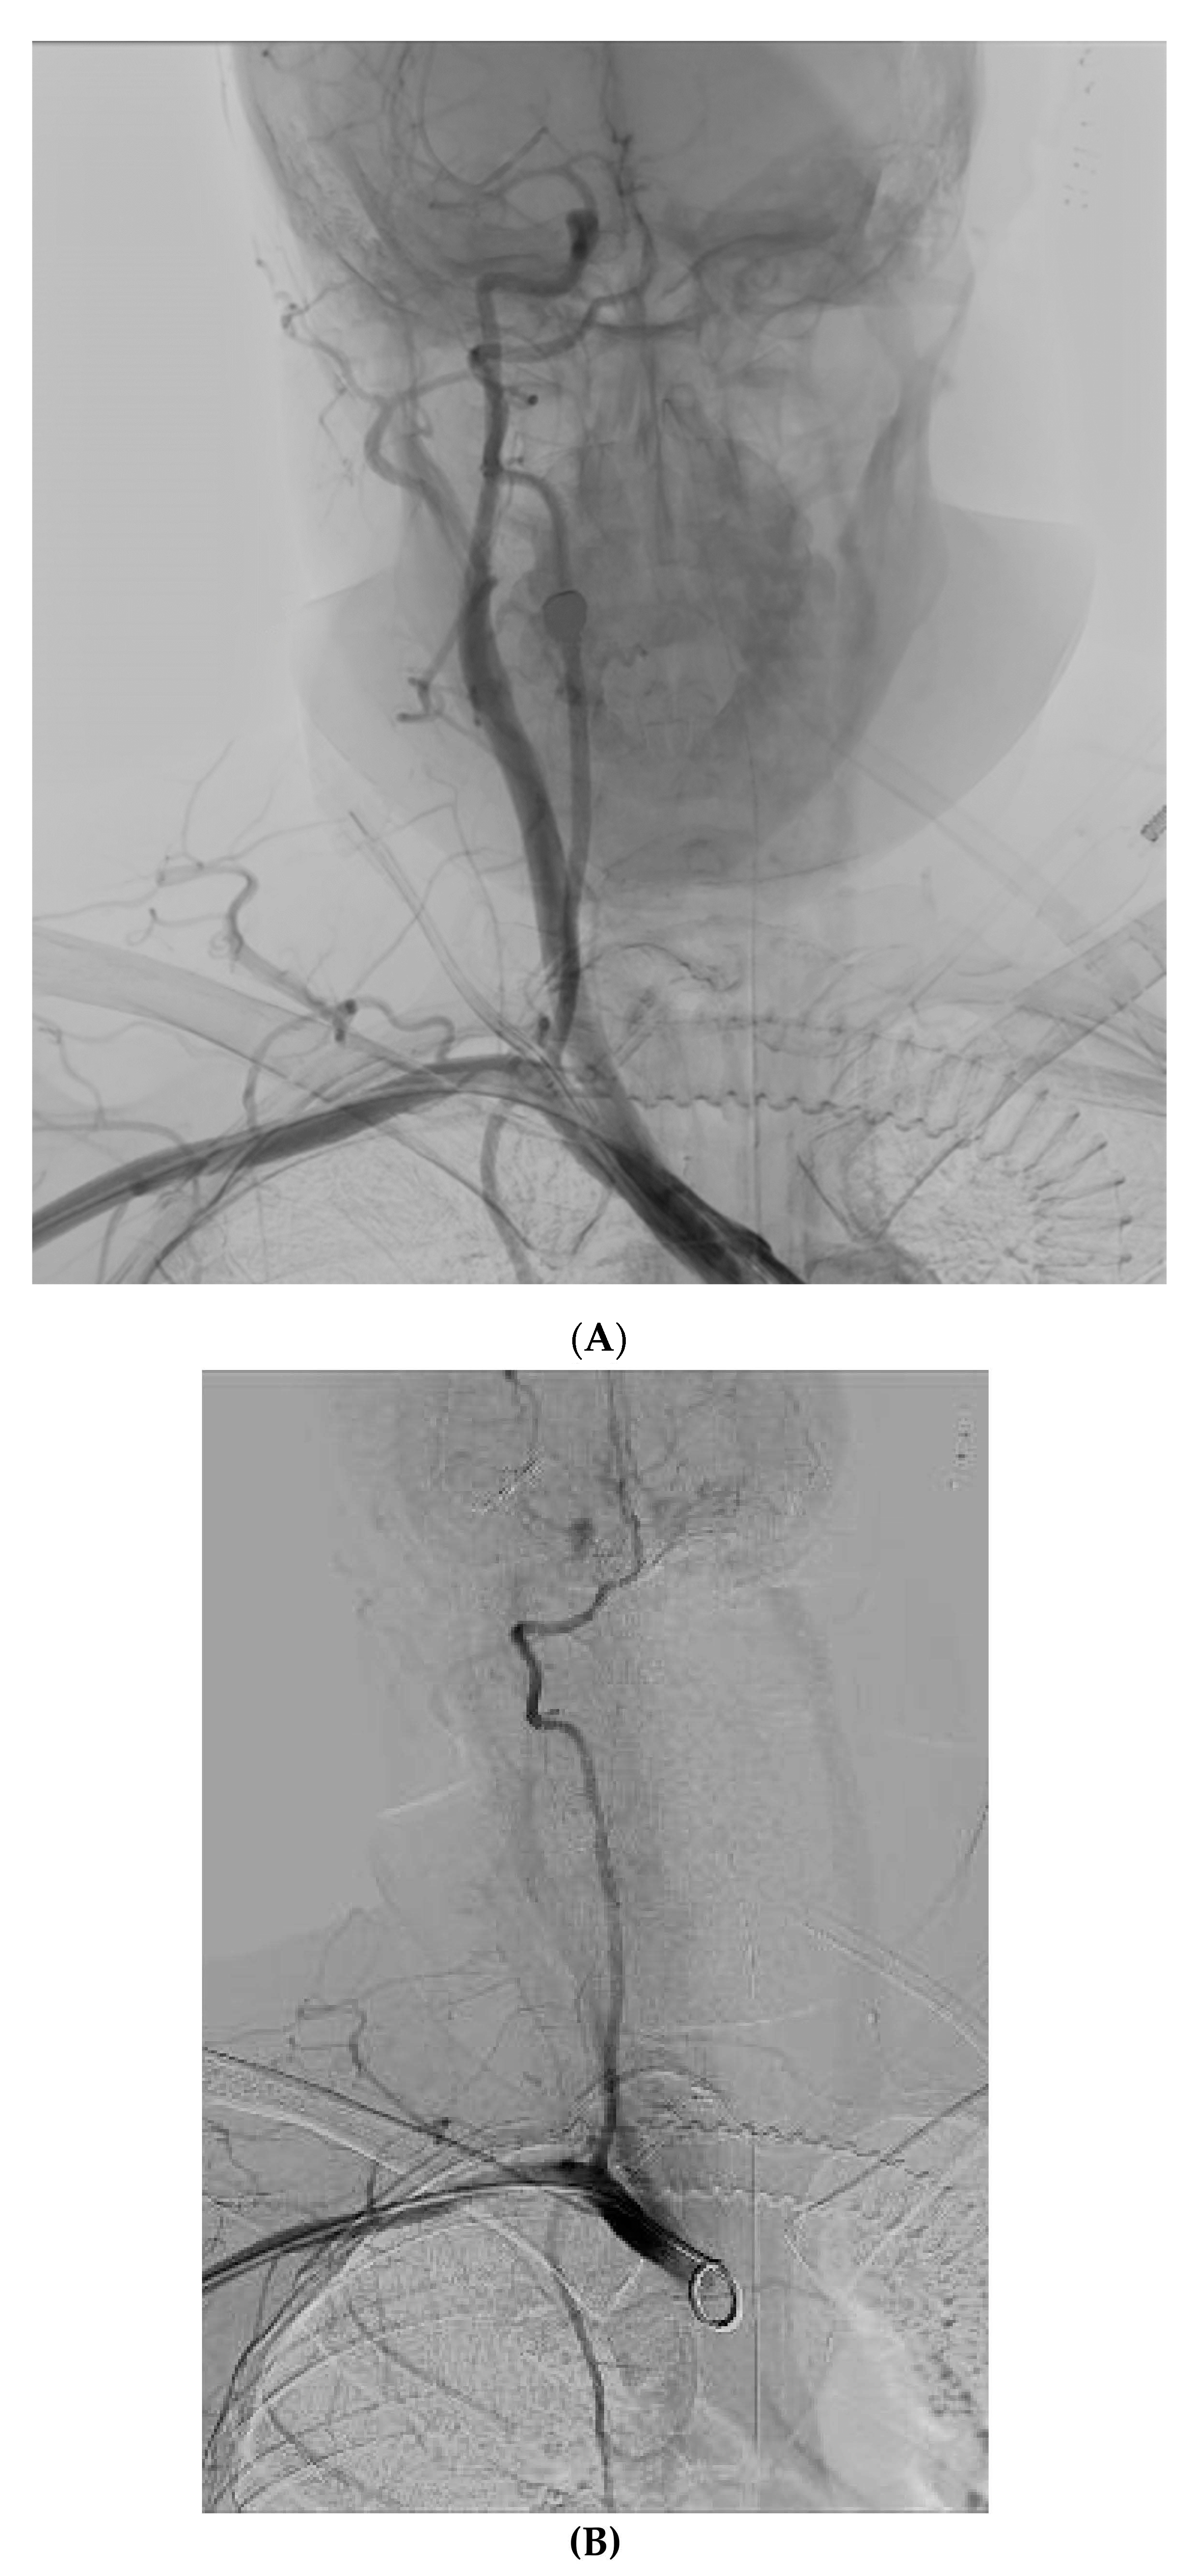

After initial patient stabilization, emergency CT angiography (Figure 2A) confirmed that the catheter had been inserted into the right common carotid artery. Vascular surgeons and interventional radiologists were consulted and external pressure application was decided as the preferred method for safe catheter removal. Alternatively, upon plan failure, internal intravascular balloon tamponade was to be used concurrently with external pressure application. The patient was transported to the Interventional Radiology Unit (Figure 2B), where a 5F sheath and catheter were inserted through the right brachial artery. The patient reported bradycardia at approximately 45–50 bpm that was noted upon patient admission to the ICU and an isoproterenol infusion was initiated and titrated to approximately 65 bpm. The patient was additionally monitored with bilateral cerebral oximetry monitoring. The catheter was slowly removed and firm external pressure was applied to the site of entry for 15 min. No significant changes were observed to the patient’s cerebral oximetry throughout the procedure. Subsequent angiography revealed no leaks or fistulae (Figure 2C). No further complications from the accidental intra-arterial catheter insertion were noted and no abnormal neurological findings were noted upon the patient’s awakening trial on his 4th and 5th day of admission.

Figure 2. (A) Digital angiography confirming right common carotid artery (CCA) catheterization with a CVC (white arrow). An angiography catheter in the arterial system is also visible (black arrow). (B) Angiography during removal of the CVC and compression of the CCA. (C) Final result after release of compression, 5 min later with no evidence of extravasation.